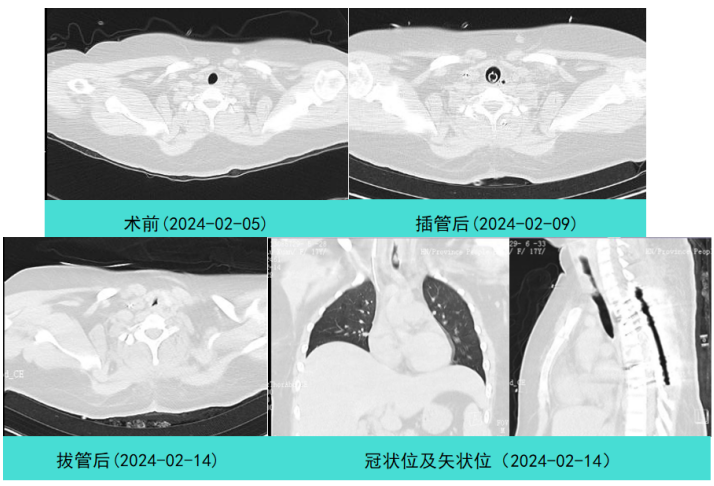

良性中心气道狭窄分为结构性和动力性(6种类型),结构性狭窄包括:管腔内生长(1型),外源性压迫(2型),瘢痕孪缩(3型),扭曲变形(4型);动力性狭窄包括:气道膜部向内膨出(5型),气道软化(6型)。对于动力性狭窄,应考虑用力呼气时的状态,通过操作者的判断,定出最合适、最接近的狭窄程度。治疗方法的制定不仅与气道狭窄程度和长度有关,还与是否存在狭窄过渡段有关。狭窄长度的计算应包括过渡区域。良性气道狭窄形态学分类的诊断方法应通过支气管镜所见及放射学检查来确定。每一个狭窄都可以用4个数字来表示,分别代表部位、类型、狭窄程度、狭窄长度。如:1344代表声门下瘢痕性挛缩性狭窄、狭窄程度>75%、狭窄长度>5 cm,这是一种非常难以处理的良性气道狭窄;2311代表气管瘢痕性蹼状网眼狭窄、狭窄程度<25%、狭窄长度<1 cm,这是一种比较容易处理的良性气道狭窄。热消融技术(APC、电凝、激光)是治疗增生性气道腔内病变(如良性肿瘤和单纯肉芽)的简单、快速的方法。但在治疗瘢痕狭窄病变时,其本身可对气道造成更重、更大范围的损伤,引起更为严重的肉芽组织增生和瘢痕形成,从而导致复发率高,且治疗次数的增加可导致狭窄病变范围增大并最终破坏软骨,导致气道塌陷,使患者彻底失去治愈的机会。电凝和APC仅适合管腔内生长的1型良性中心气道狭窄,并不适合其他类型良性中心气道狭窄的治疗。即便如此,基底部的处理也应避免使用此类治疗方法。针形电刀与气道黏膜接触面极小,不会造成损伤面扩大,瘢痕性气道狭窄的治疗宜选用针形电刀进行切割、松解。因激光也有切割的作用,因此也可选用激光治疗,钬激光、铥激光控制烧灼深度最浅可达0.4 mm,因此更适合良性瘢痕增生性气道狭窄的治疗。冷冻治疗分为冷冻切除(简称冻切,cryoextraction)及冷冻消融(简称冻融,cryoablation)。对于腔内生长的病变可采用冻切治疗,由于容易出血,其安全性不如热消融技术。对于瘢痕病变,冻切技术无法实施,则采用冻融治疗,冻融治疗不促进肉芽组织增生。与热消融相比,冷冻不易导致软骨损伤。通常在热消融治疗接近气道壁时或球囊扩张后采用冻融治疗处理剩余病变,有利于减轻瘢痕再狭窄发生的速度与程度。严重气道狭窄在开通气道前不要使用冻融,因其可引起气道水肿,加重气道狭窄,从而导致窒息。因此,冻融治疗后肺部体征监测及气管镜复查十分重要。机械扩张技术包括球囊扩张和硬质支气管镜扩张,并发症有气道撕裂、再狭窄、出血。(1)球囊扩张:是治疗瘢痕性气道狭窄最主要的技术,其优势是患者治疗后无明显的狭窄段延长,狭窄复发时再狭窄的程度比热消融治疗后轻得多,有利于维持气道复张的疗效。对气管黏膜损伤小,可以在软镜下应用,但需要中断通气。对于挛缩、韧性较强的瘢痕,可先用针形电刀进行切割以松解瘢痕;避免直接暴力球囊扩张,导致气道膜部的撕裂伤。(2)硬质支气管镜扩张:其优势是扩张时不需要中断通气,安全性更好。针对瘢痕肉芽组织增生导致介入治疗后的气道再狭窄,可采用气道狭窄部位局部应用药物的方法抑制瘢痕肉芽组织增生。介入治疗后气道再狭窄可选择的治疗药物有:糖皮质激素、丝裂霉素C、曲尼斯特、紫杉醇等。通过直接植入放射性物质(最常用铱-192)或经过可弯曲支气管镜近距离照射气道瘢痕肉芽组织,促使成纤维细胞凋亡。气道支架置入首选硅酮支架,禁用金属裸支架。支架治疗应作为良性气道狭窄最后选择的治疗技术,启动气道支架治疗的指征:①应用前述各种治疗方法疗效不佳,不能维持气道通畅;②在确定外科手术前临时放置;③外压性气道狭窄;④气道软化、塌陷且无法或不准备行外科手术治疗。病例1:17岁,女性,骨折术后肺炎插管,拔管后(2月14日)气道明显狭窄(图3)。2月15日评估:HR 113次/min,R 24次/min,静息下SpO2 97%(FiO2 50%),咳嗽及说话后喘鸣,有阵发性血氧下降。会诊后拟行急诊介入治疗。2月15日无痛气管镜示:声门下腔黄色及乳白色膜状坏死物,气管上段大量黄色坏死物并管腔重度阻塞,仅见小孔,以冷冻法清除坏死物后管腔通畅(图4)。术后气促明显改善,无需吸氧。病例2:77岁,女性,呼吸困难2个月,加重3天,于2023年12月2日入院(2023年9月气管插管,插管后20余天后拔管)。入院当天查体:HR 125次/min,R 30次/min,静息下SpO2 96%(高流量FiO2 30%),PaCO2 56 mmHg。患者术前影像如图5所示。12月3日查体:HR 140次/min,R 35次/min,BP 190/90 mmHg,SpO2 68%~75%(FiO2 100%),躁动不安,急查血气分析:PaCO2 89 mmHg。紧急床旁无创通气支持下气管镜:气管上段狭窄80%以上,较多黄白黏稠分泌物在狭窄口随呼吸摆动,予抽吸后SpO2升至98%,见狭窄处直径约3 mm,外径5.2 mm,软镜无法进入,遂置入导丝,10#球囊扩张多次,狭窄部位增宽,外径4 mm气管镜引导6.0号气管导管经口插管成功(图6)。插管后患者HR 98次/min,复查血气分析示PaCO2 41 mmHg,氧合指数300 mmHg以上。12月4日气管镜示:右鼻旁路进镜,缓慢退气管导管至声门,距声门3 cm处狭窄,直径7 mm,予12#球囊扩张1 min,2次,未见出血,扩张后直径约12 mm,地塞米松局部保留,气管导管复位(图7)。12月5日拔除气管导管。12月6日气管镜示:气管上段瘢痕狭窄(管径10~12 mm),少许膜状坏死、未见肉芽,予以清除坏死物,7点、11点冻融,术毕注入地塞米松5 mg(图8)。12月13日气管镜示:气管上段瘢痕狭窄(管径12 mm左右),少许膜状坏死、未见肉芽,予以清除坏死物,7点、11点冻融,术毕注入地塞米松5 mg(图9)。